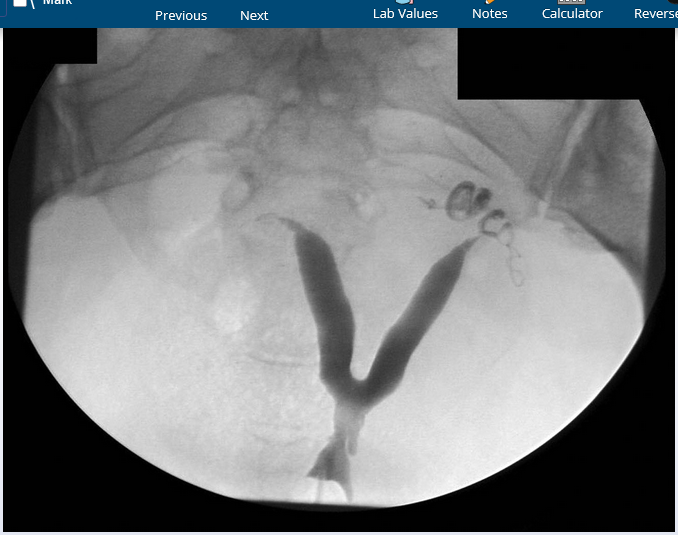

22yo with new generalized tonic-clonic seizure, 3-week hx progressive headaches, fever, nasal congestion, & rhinorrhea. HIV -.

brain abscess

likely staph a, viridians strep, or anaerobes